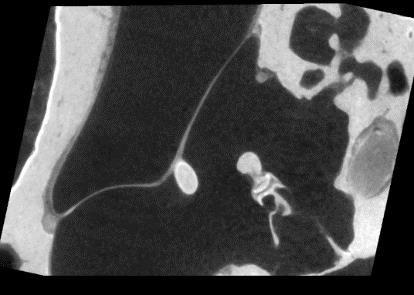

Purpose: Middle ear infection is the most prevalent inflammatory disease, especially among the pediatric population. Current diagnostic methods are subjective and depend on visual cues from an otoscope, which is limited for otologists to identify pathology. To address this shortcoming, endoscopic optical coherence tomography (OCT) provides both morphological and functional in-vivo measurements of the middle ear. However, due to the shadow of prior structures, interpretation of OCT images is challenging and time-consuming. To facilitate fast diagnosis and measurement, improvement in the readability of OCT data is achieved by merging morphological knowledge from ex-vivo middle ear models with OCT volumetric data, so that OCT applications can be further promoted in daily clinical settings. Methods: We propose C2P-Net: a two-staged non-rigid registration pipeline for complete to partial point clouds, which are sampled from ex-vivo and in-vivo OCT models, respectively. To overcome the lack of labeled training data, a fast and effective generation pipeline in Blender3D is designed to simulate middle ear shapes and extract in-vivo noisy and partial point clouds. Results: We evaluate the performance of C2P-Net through experiments on both synthetic and real OCT datasets. The results demonstrate that C2P-Net is generalized to unseen middle ear point clouds and capable of handling realistic noise and incompleteness in synthetic and real OCT data. Conclusion: In this work, we aim to enable diagnosis of middle ear structures with the assistance of OCT images. We propose C2P-Net: a two-staged non-rigid registration pipeline for point clouds to support the interpretation of in-vivo noisy and partial OCT images for the first time. Code is available at: https://gitlab.com/nct\_tso\_public/c2p-net.